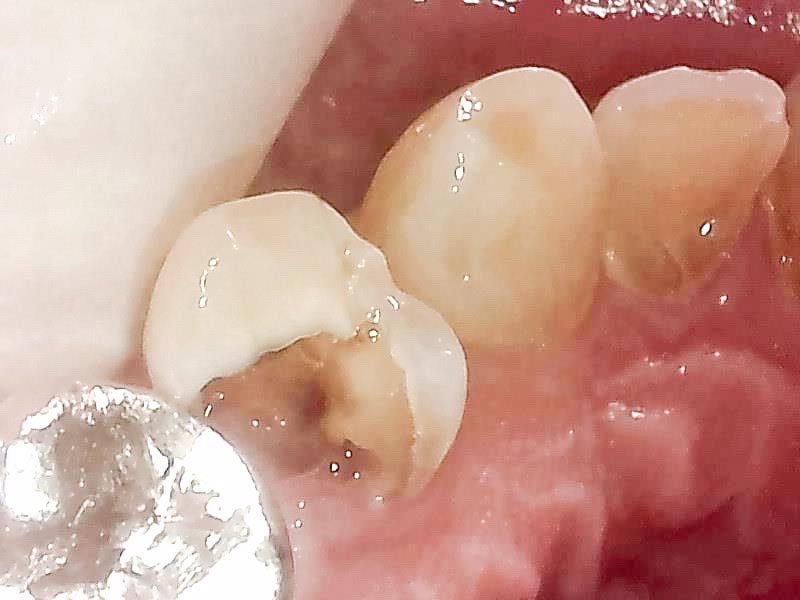

カリソルブイ 違った!カリソルブを虫歯に塗布し、30秒放置します。

するとむし歯は、とても柔らかく溶解するので、手持ちの道具で掻き出していきます。

ほとんどのむし歯を削らないで、溶かしていく事ができます。

カリソルブでむし歯除去後です。